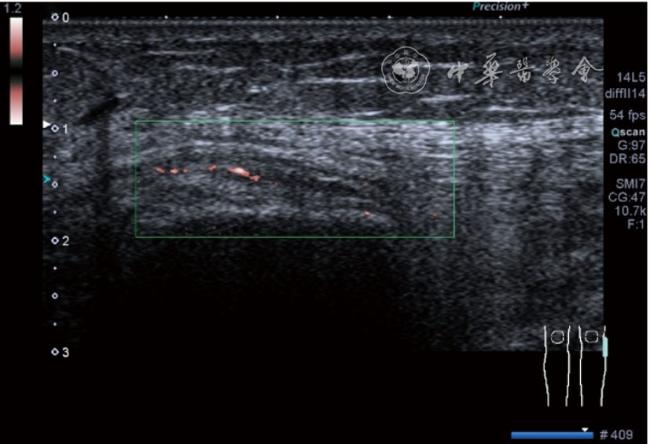

患者采取侧卧位,患肢在上,屈膝20°。应用10~18 MHz高频线阵探头,扫查深度1~3 mm。长轴和短轴结合双侧对比扫查。超声影像学所见:短轴可见卡压腓总神经近端增粗,面积增大;长轴可见腓总神经卡压处变细,其近侧肿胀、回声减低,而在卡压远侧则表现正常(图35);一些受压严重者可以出现神经周围积液,卡压神经部位的筋膜增厚(图36);受压神经内血流增加对临床诊断意义更大(图37);探头在病变神经处加压常可引起神经刺激症状。腓总神经支配的肌肉有失神经支配改变,表现为肌肉回声增高和肌肉萎缩(图38)。

图37 受压腓总神经内血流增加超声图像